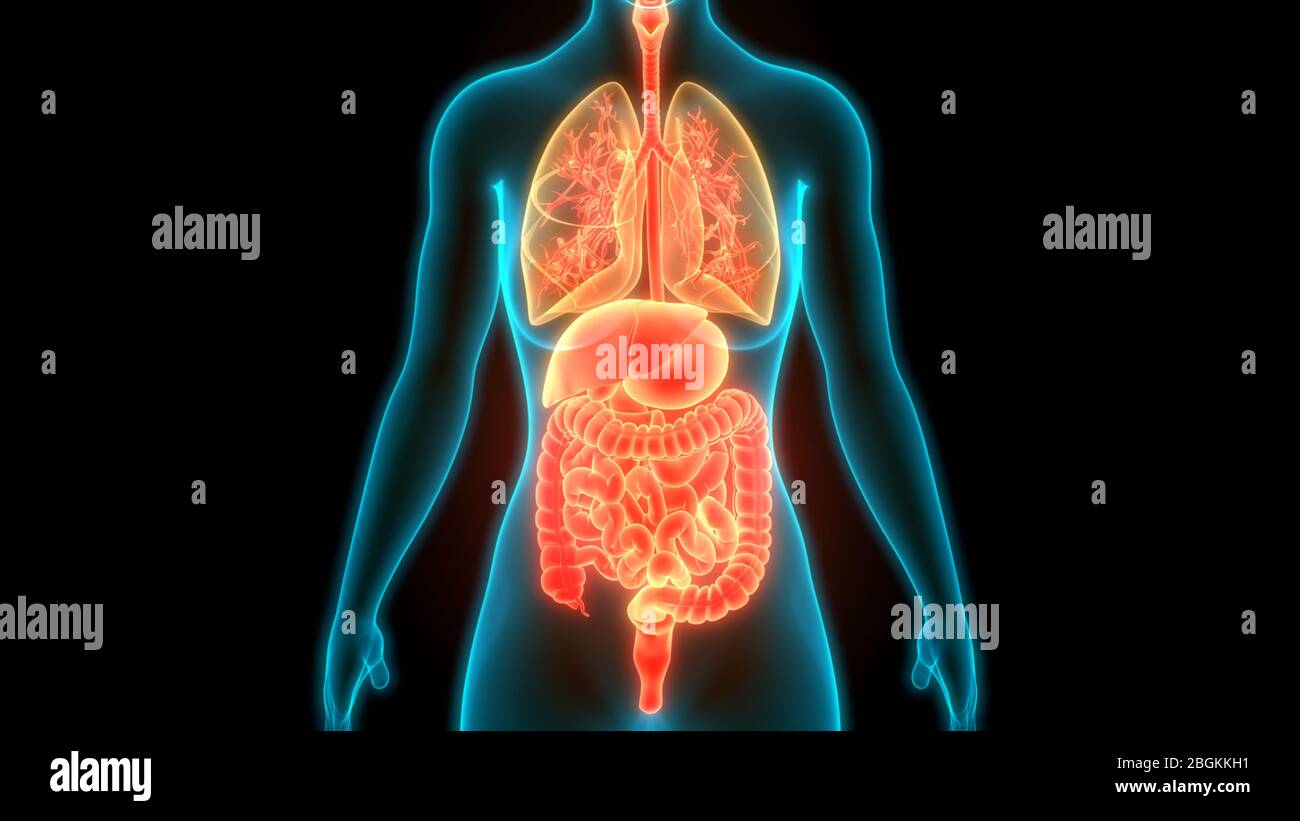

Human Complete Internal Organs Anatomy Stock Photohttps://www.alamy.com/image-license-details/?v=1https://www.alamy.com/human-complete-internal-organs-anatomy-image354474317.html

Human Complete Internal Organs Anatomy Stock Photohttps://www.alamy.com/image-license-details/?v=1https://www.alamy.com/human-complete-internal-organs-anatomy-image354474317.htmlRF2BGKKH1–Human Complete Internal Organs Anatomy